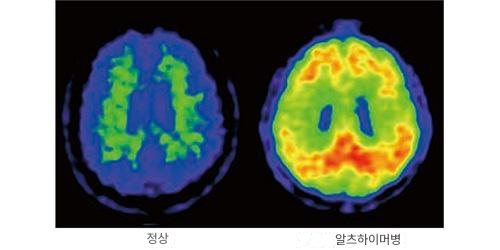

이미지3 정상자와 알츠하이머병의 뇌 아밀로이드 PET

정상적인 사람은 아밀로이드가 침착하지 않지만 알츠하이머병의 경우 뇌에 아밀로이드가 침착됩니다(빨강~노란색 부분)